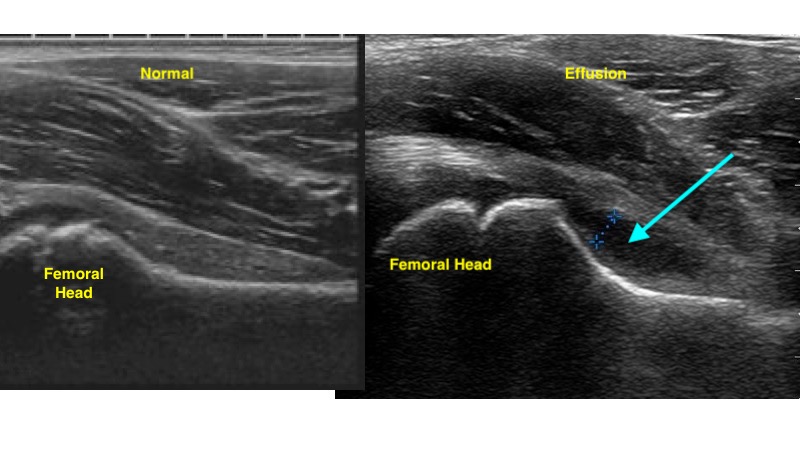

- Effusion is identified as a hypoechoic area along the femoral head/ neck within the hyperechoic capsule.5 (Fig. 7)

- Figure 7. Ultrasound demonstrating normal hip (left) and hip effusion (right)